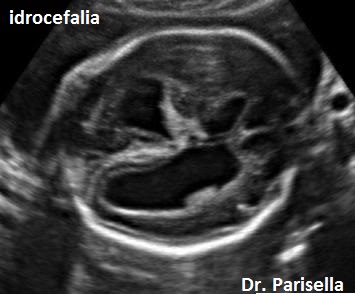

Le anomalie facciali consistono in labiopalatoschisi e micrognazia. Le anomalie degli arti consistono in ipoplasia delle falangi distali. Le anomalie cerebrali comprendono l'agenesia del corpo calloso e l'idrocefalia.